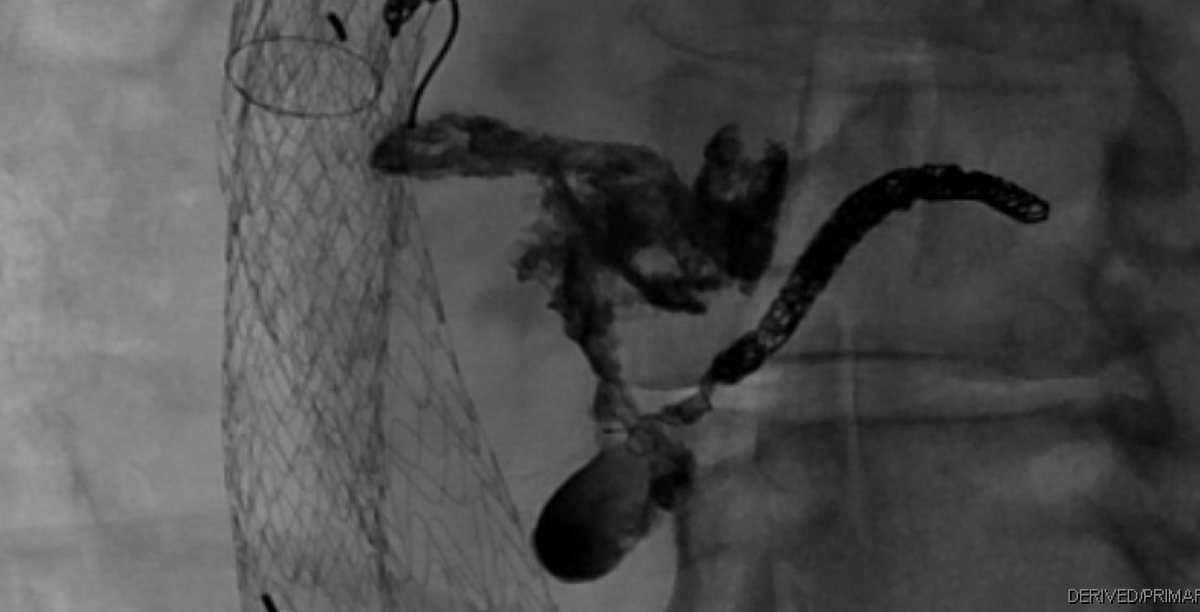

40 yo w/cirrhosis and RLQ ostomy w/ recurrent bleeding from parastomal varices. Transjugular transhepatic variceal sclerosis performed w/STS foam and lipiodol. TIPS on the way out. No further bleeding. Sunil Narayan, MD thandoro SIR RFS Society of Interventional Radiology @GESTSymposium JVIR

2 years status-post placement of a flow diverting stent to treat an enlarging splenic artery aneurysm. Aneurysm remains thrombosed, splenic artery patent. Great collaborative case with our neurosurgery colleagues. #IRad Society of Interventional Radiology SIR RFS Albany IR Albany Medical Center Department of Neurosurgery

2 years status-post placement of a flow diverting stent to treat an enlarging splenic artery aneurysm. Aneurysm remains thrombosed, splenic artery patent. Great collaborative case with our neurosurgery colleagues. #IRad <a href="/SIRspecialists/">Society of Interventional Radiology</a> <a href="/SIRRFS/">SIR RFS</a> <a href="/AlbanyIR/">Albany IR</a> <a href="/AMCNeurosurgery/">Albany Medical Center Department of Neurosurgery</a>